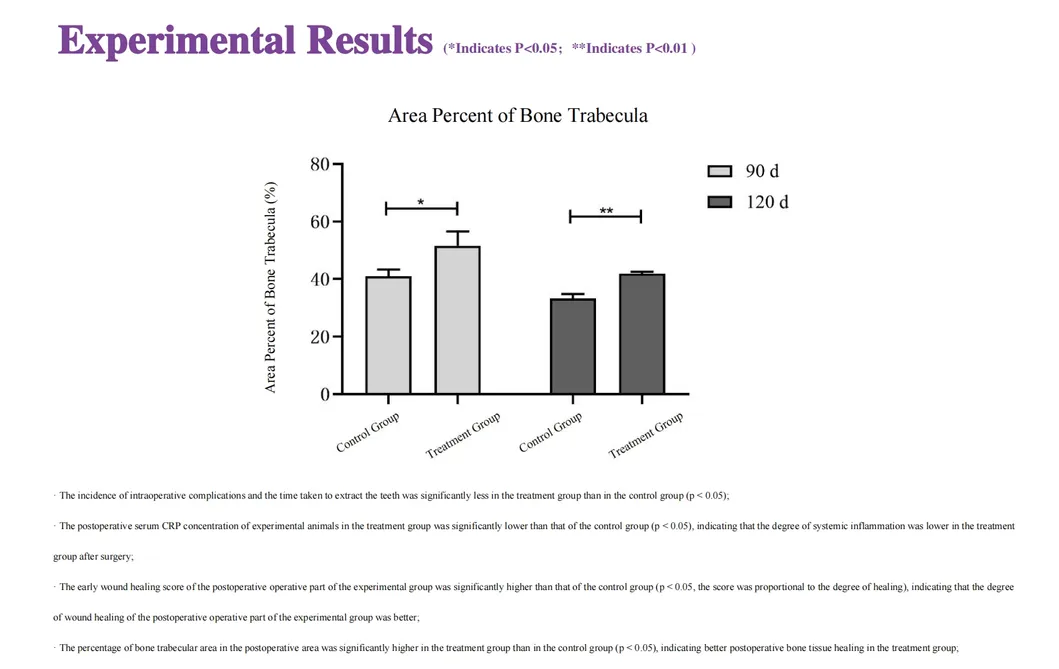

This study evaluated the effectiveness of state-of-the-art dental tools for veterinary use. The treatment group utilized the revolutionary Pneumatic Dental Elevator Kit. Critical factors observed included physiological parameters, intraoperative complications, extraction duration, and socket damage. Rigorous statistical analysis highlights the superior performance of these advanced tools.